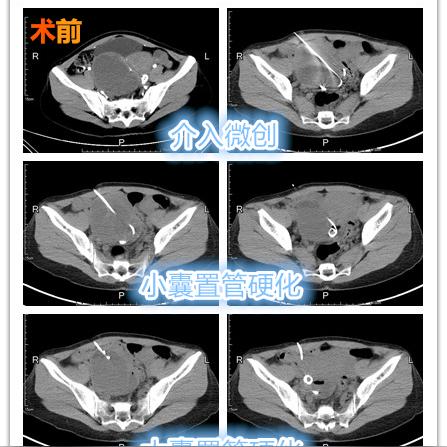

卵巢囊肿是指卵巢内出现的液体填充的囊状结构,大多数卵巢囊肿为良性,不会引起严重症状,部分卵巢囊肿可能需要治疗,因为它们可能引起疼痛、不孕或其他并发症。

腹腔镜手术是目前治疗卵巢囊肿最常用的方法之一,通过腹腔镜技术,医生可以在不开刀的情况下,通过微小切口进行手术,从而减少对患者的创伤,据统计,约90%的卵巢囊肿患者通过腹腔镜手术可以成功治疗。